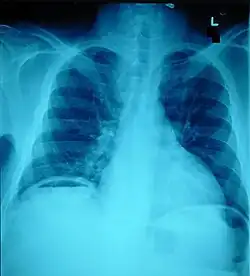

The small intestine takes up a large part of the abdomen and is likely to be damaged in penetrating injury.[5] The bowel may be perforated.[4] Gas within the abdominal cavity seen on CT is understood to be a diagnostic sign of bowel perforation; however intra-abdominal air can also be caused by pneumothorax (air in the pleural cavity outside the lungs that has escaped from the respiratory system) or pneumomediastinum (air in the mediastinum, the center of the chest cavity).[4] The injury may not be detected on CT.[4] Bowel injury may be associated with complications such as infection, abscess, bowel obstruction, and the formation of a fistula.[4] Bowel perforation requires surgery.[4]

Ten percent of people with polytrauma who had no signs of abdominal injury did have evidence of such injuries using radiological imaging.[1] Diagnostic techniques used include CT scanning, ultrasound,[1] and X-ray.[7] X-ray can help determine the path of a penetrating object and locate any foreign matter left in the wound, but may not be helpful in blunt trauma.[7] Diagnostic laparoscopy or exploratory laparotomy may also be performed if other diagnostic methods do not yield conclusive results.[5]